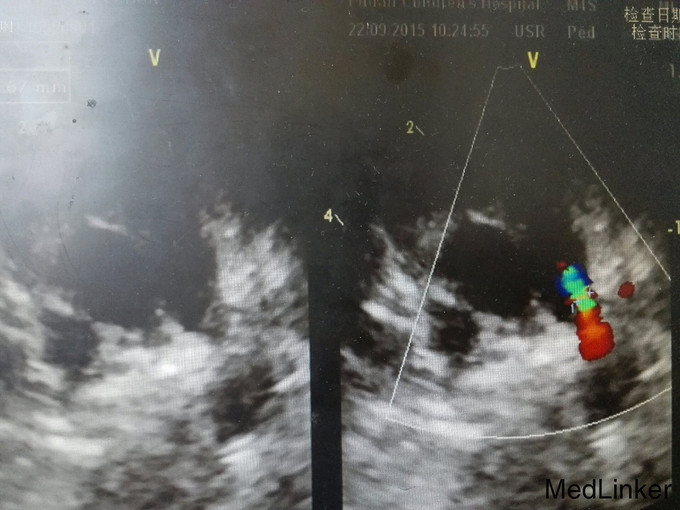

查体:神清,精神可,浅表淋巴结未及肿大,全身皮肤无皮疹、出血点,颈软,咽不红,扁桃体无肿大,双肺呼吸音粗,未闻及明显干湿性罗音。心前区未见隆起,心前区抬举未见,心尖搏动位位于第四肋间左乳线外0.5cm,震颤未及心界不大,心率100次/分,心律齐,心音有力,lsb2-3肋间可及ii/6级连续性杂音。腹软,腹部无压痛及反跳痛,肝脾肋下未及,神经系统检查(-)。双侧桡动脉、股动脉、足背动脉搏动正常。 辅助检查:心超(09.17):动脉导管未闭(3mm)。入院后行胸片检查:两肺血稍多。

诊断:动脉导管未闭 治疗:动脉导管未闭封堵术